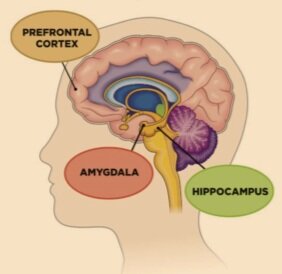

Difference Between the Amygdala and the Prefrontal Cortex

The Cortex and the Amygdala - SOAR Library - SOAR

PTSD, the Hippocampus, the Amygdala: How Trauma Changes the Brain

The Limbic System